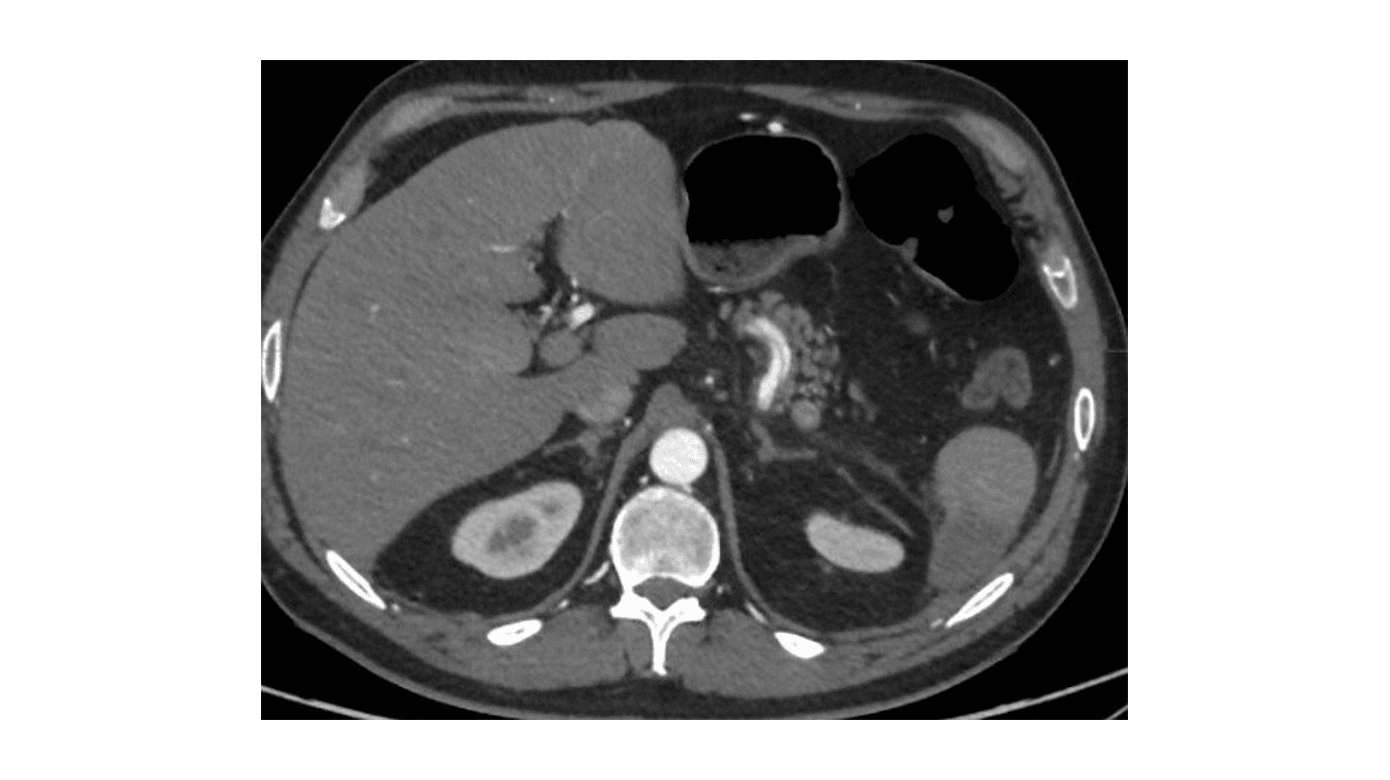

En CT af abdomen og en CT-angiografi viste miltinfarkt og dissektion i tr. coeliacus videre ud i a. hepatica communis og a. lienalis med trombe (Figur 1). En kontrol-CT efter fire dage viste uændrede forhold.